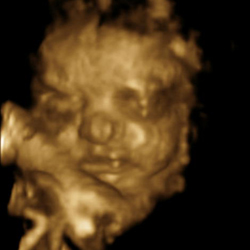

Been waiting ages to go get this done and it turned out to be worth the money and trip to Dublin from Leitrim! First proper look at the baby complete with smiles, waves & yawns in 2D, 3D and 4D!

Here’s some of the better poses (the first one is probably our favorite with the baby’s arms under it’s head!):

Those are really bringing the images to a new level.

More than a grainy ultrasound, you can see what the wee one actually looks like.

They still kind of freak me out a bit though…